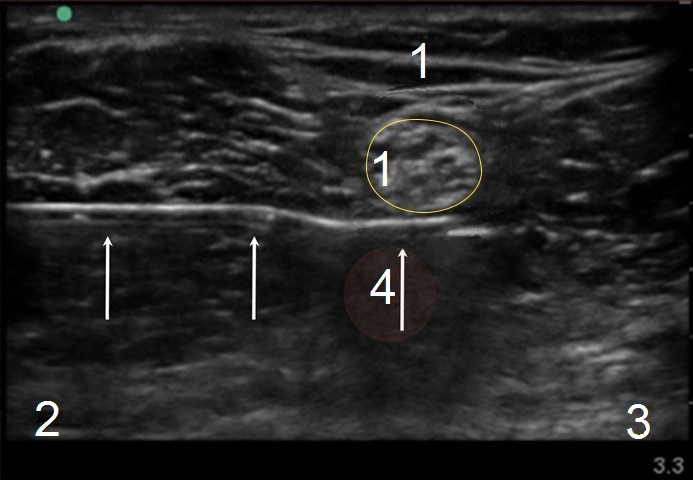

膝窩神経ブロック注射のイメージ

矢印: 針

脛骨神経

外側

内側

膝窩動脈